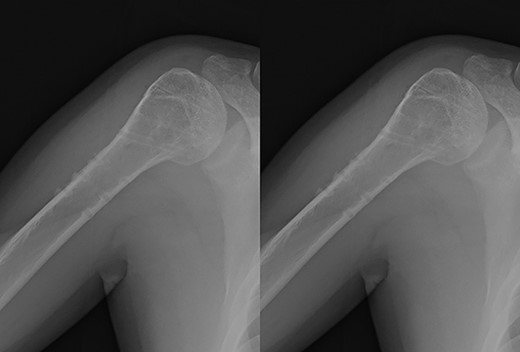

Postoperative radiographic and CT evaluations showed reduced fractures on the humeral head and surgical neck (Fig. 7). At 24 months of postoperative follow-up, radiographic and CT evaluations showed no signs of osteoarthritis or reimpression (Fig. 8). Two years after the primary surgery, we performed implant removal at the patient’s request (Fig. 9). When performing implant removal, we additionally performed a second-look evaluation with arthroscopy to assess the degree of healing in the joint. We noted no impression or exposure of cartilage callus on either side of the humeral head or glenoid (Fig. 10).

Post-implant removal X-ray showing that the alignment had been maintained.